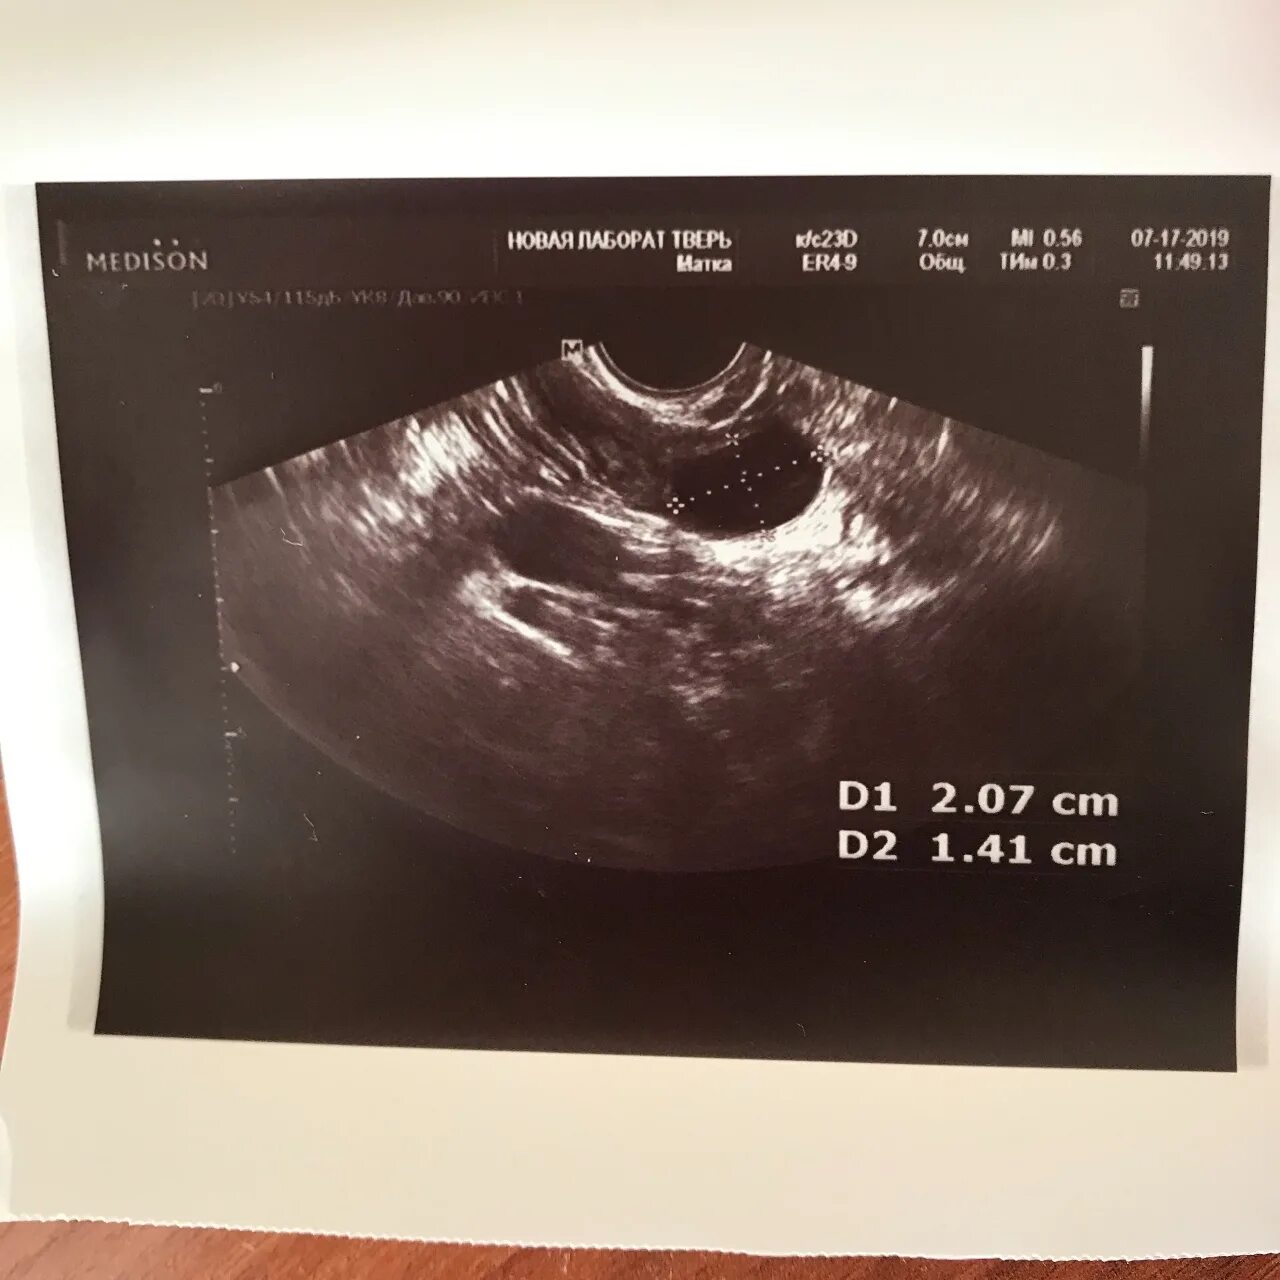

Фолликул 11 мм